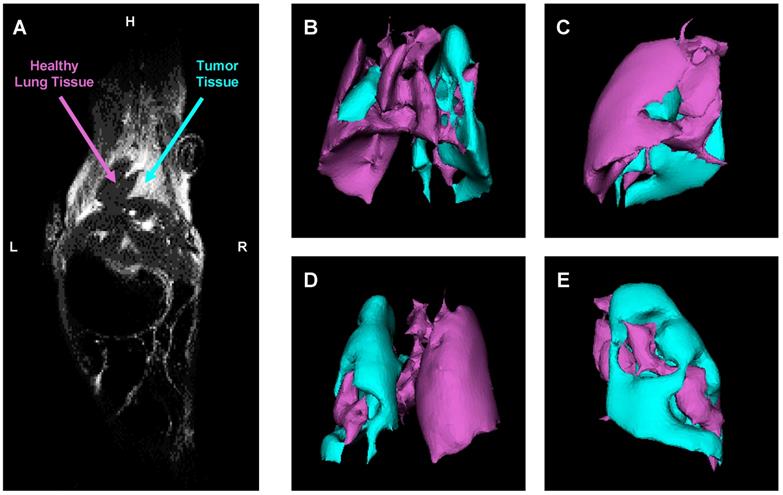

An orthotopic mouse model of human lung cancer was developed in our lab according to a protocol approved by the Institutional IACUC. According to the protocol, NSCLC cancer cells (human A549) transfected with luciferase in a medium containing 5 μmole of EDTA were administered intratracheally to the mouse lung through a catheter. It was shown that slight disruption of the pulmonary epithelium or the surfactant layer by co-administration of either pancreatic elastase or EDTA allowed significantly better tumor engraftment [45]. Suspension of cancer cells and this concentration of EDTA displayed no adverse side effects in test animals. Rapid growth of lung tumor occurred in 80% of animals. The progression of tumor growth was monitored using bioluminescent (IVIS) and magnetic resonance imaging systems. As an example of MRI image processing, a representative images of an entire mouse and mouse lungs with tumor are shown on Figure 6A-E. MRI was performed using a 1 T M2™ whole body scanner and images were recorded in Fast Spin Echo sequence. Magnetic resonance signal and tumor volume were calculated using VivoQuant 1.21 software. The analysis of lung images by VivoQuant software is shown on the Fig 6B-E images which show rotated representative image of lungs with tumor where a where a bright rich purple (orchid) color represents a healthy lung tissue, while cyan - tumorous tissue. Image analysis clearly shows the development of lung tumor and validates the orthotopic lung tumor model. Bioluminescence images of transfected NSCLC cells also support the development of lung cancer (Figure 7A).

Figure 6

Evaluation of orthotopic model of human NSCLC in nude mice by a magnetic resonance imaging (MRI). A - Representative MRI image of a mouse with lung tumor. B-E - Computer analysis of representative MRI image of mouse lungs. Bright rich purple (orchid) color represents a healthy lung tissue, while cyan - tumor tissue (B - top; C - right; D - bottom; E - left).